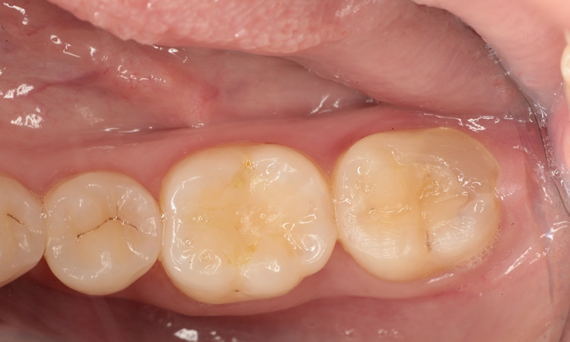

Première molaire supérieure, en 100 minutes

Un inlay CEREC Tessera

La restauration lors d’une consultation unique s’est avérée être une solution particulièrement efficace et confortable pour cette patiente, qui devait effectuer un trajet de 50 kilomètres pour se rendre au cabinet. Un inlay très esthétique a pu être réalisé avec CEREC Tessera.

Avant : Restauration en céramique fracturée réalisée à partir d’une vitrocéramique renforcée à la leucite après une durée d’utilisation clinique de 12 ans.

Après : Restauration fabriquée en consultation à partir d’une céramique avancée au disilicate de lithium CEREC Tessera.

Dr. Sven Rinke

Hanau, Allemagne